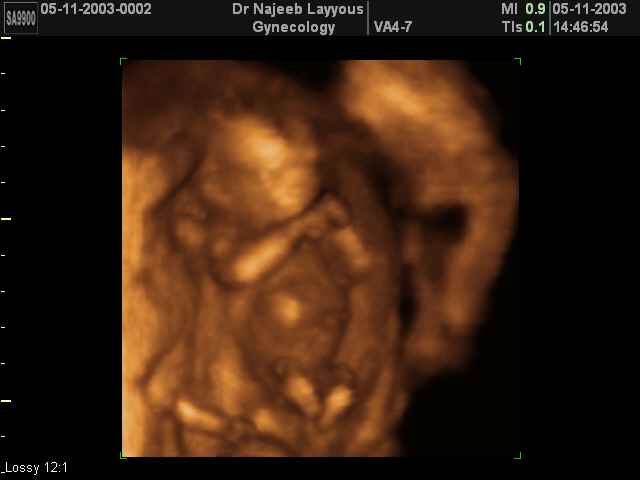

“So what will it be: Wanted fetuses are charming, complex, REM-dreaming little beings whose profile on the sonogram looks just like Daddy, but unwanted ones are mere ‘uterine material’? How can we charge that it is vile and repulsive for pro-lifers to brandish vile and repulsive images if the images are real? To insist that the truth is in poor taste is the very height of hypocrisy. Besides, if these images are often the facts of the matter, and if we then claim that it is offensive for pro-choice women to be confronted by them, then we are making the judgment that women are too inherently weak to face a truth about which they have to make a grave decision. This view of women is unworthy of feminism.”

Naomi Wolf, feminist author and advocate of legal abortion, in “Our Bodies, Our Souls”, The New Republic, 10/15/1995